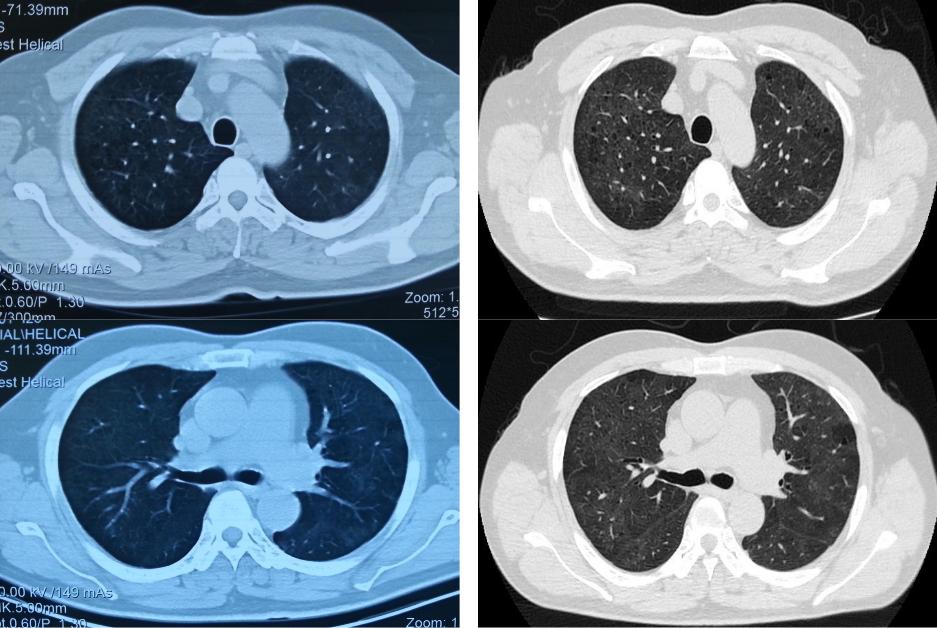

后来,患者到中日医院就诊,这是2015-9-30在中日医院的胸部CT(右)与2015-8-20胸部CT(左)有进一步吸收的对比: